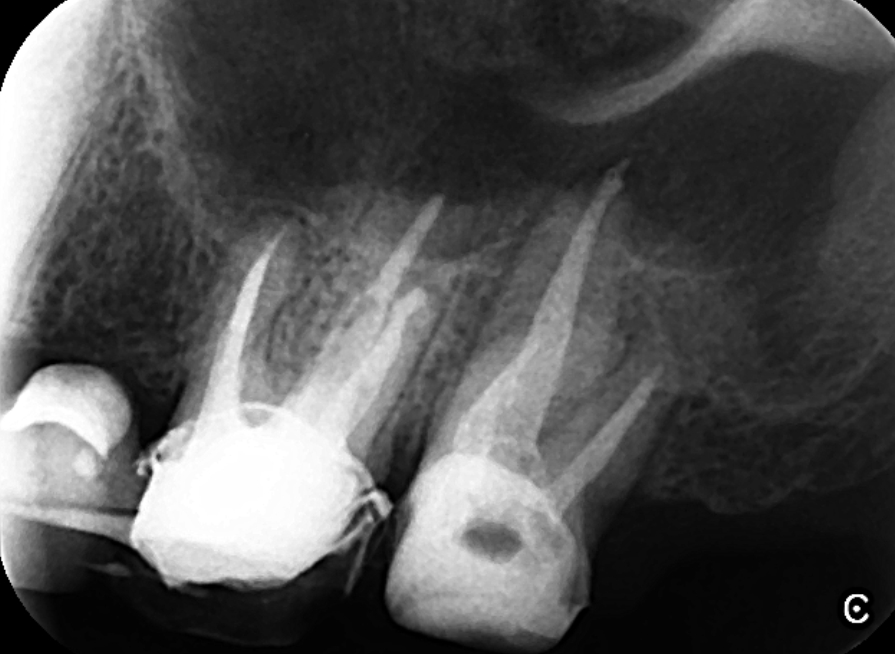

上顎第一大臼歯と第二大臼歯の精密根管治療を行いました。画像は、根管充填時のレントゲン写真です。